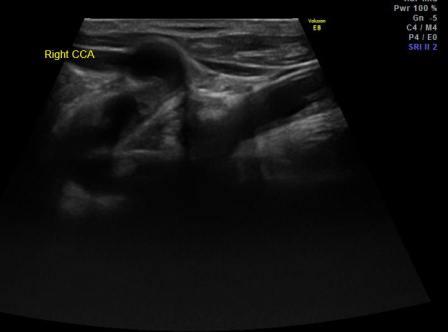

Заголовок сообщения: ОСА пошла винтом.

Вот причудливая ОСА.

raznoe_2.jpg

raznoe_1.jpg